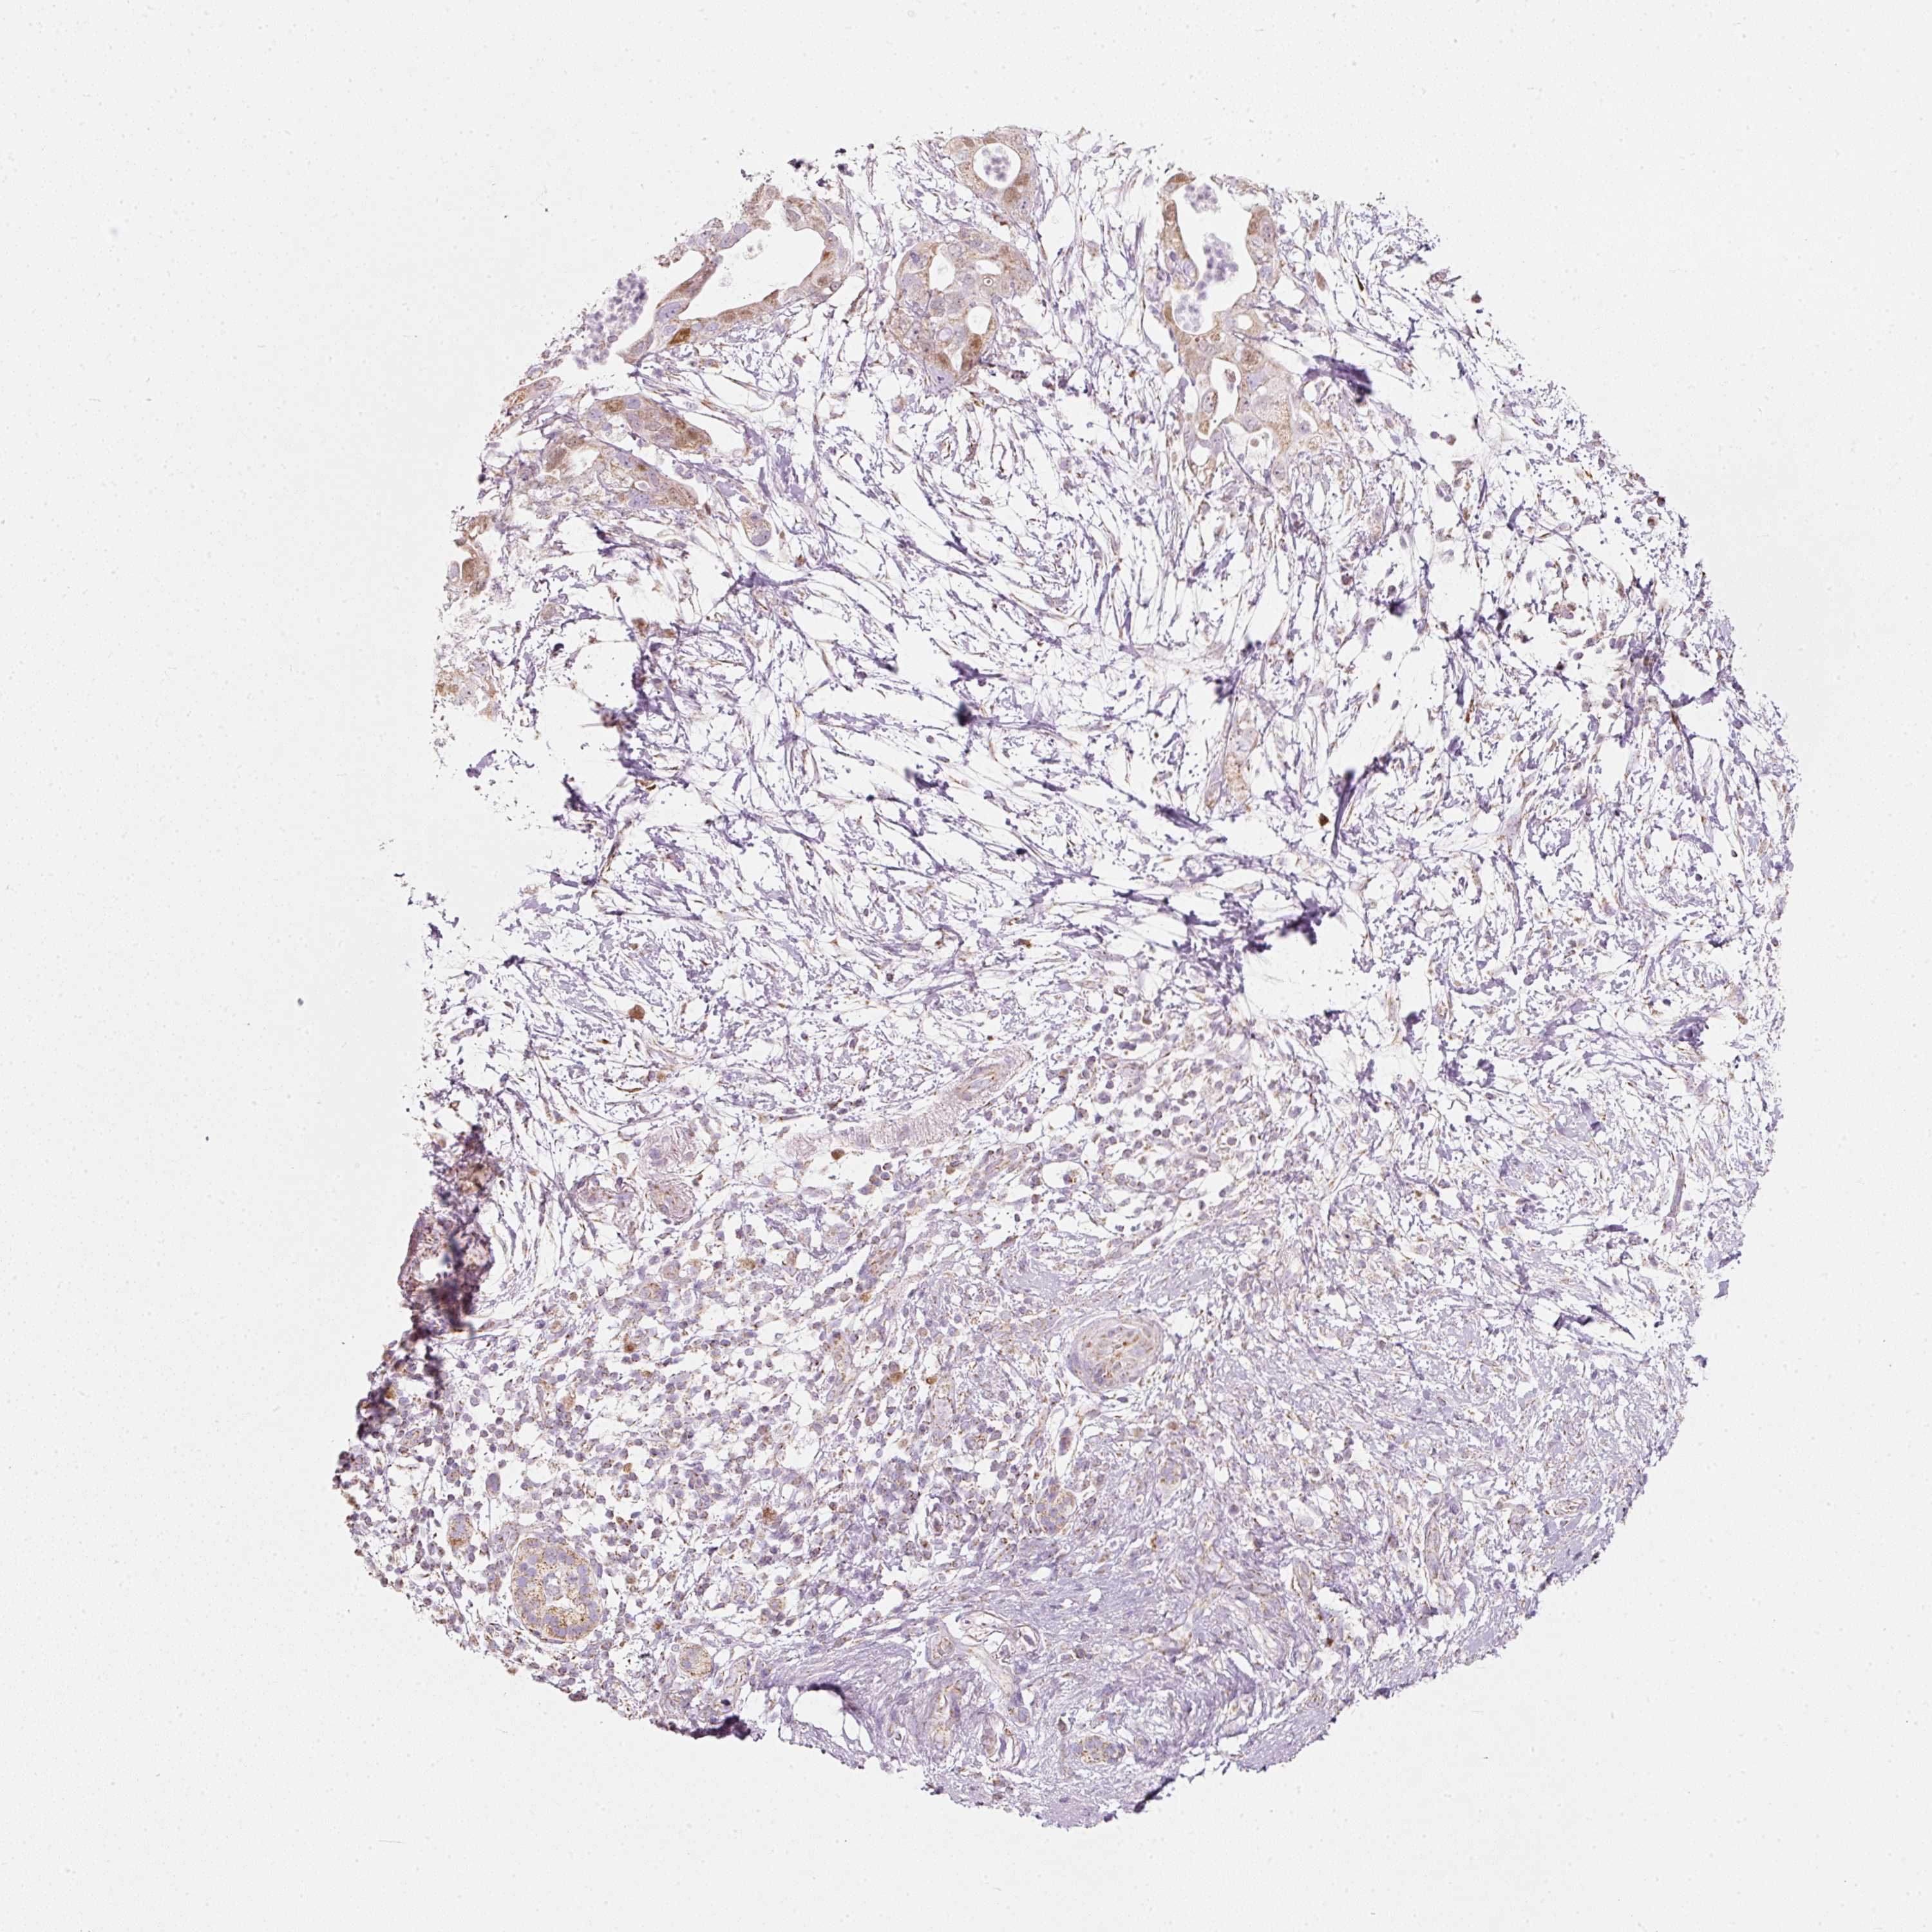

PANCREATIC CANCER - Protein expressioni

A mouse-over function shows sample information and annotation data. Click on an image to view it in a full screen mode. Samples can be filtered based on level of antibody staining by selecting one or several of the following categories: high, medium, low and not detected. The assay and annotation is described here.

Note that samples used for immunohistochemistry by the Human Protein Atlas do not correspond to samples in the TCGA dataset.

Antibody stainingi

Antibody staining in the annotated cell types in the current human tissue is reported as not detected, low, medium, or high, based on conventional immunohistochemistry profiling in selected tissues. This score is based on the combination of the staining intensity and fraction of stained cells.

Each image is clickable and will lead to virtual microscopy that enables deeper exploration of all samples and also displays staining intensity scores, fraction scores and subcellular localization as well as patient and tissue information for each sample.

Antibody HPA054422

Antibody HPA060360

Adenocarcinoma, NOS